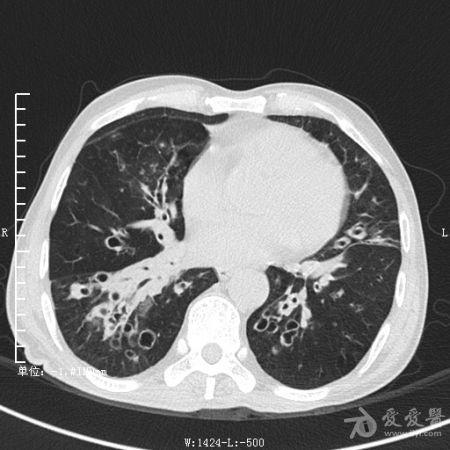

典型支气管扩张及肺水肿CT片

典型支气管扩张肺水肿